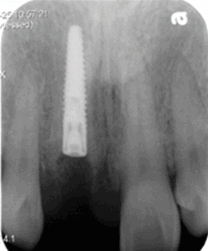

前牙即刻修復(fù)病例一例